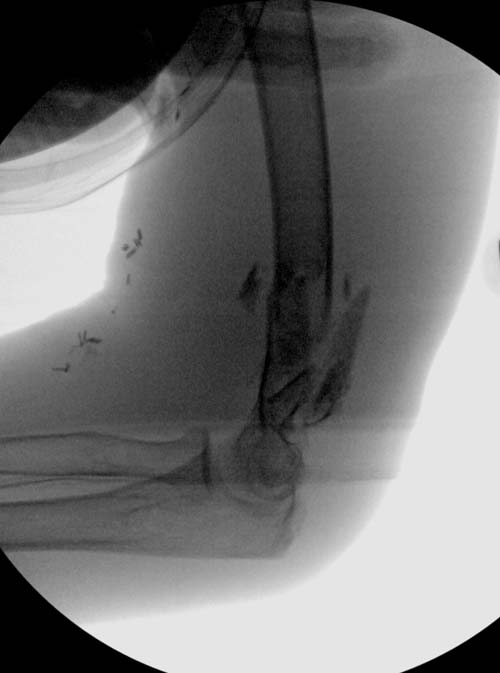

Через пару дней операция на дистальном плече. У него, кроме переломов

бедра, имеется перелом позвонков, и нагрузку на конечность в ближайщее